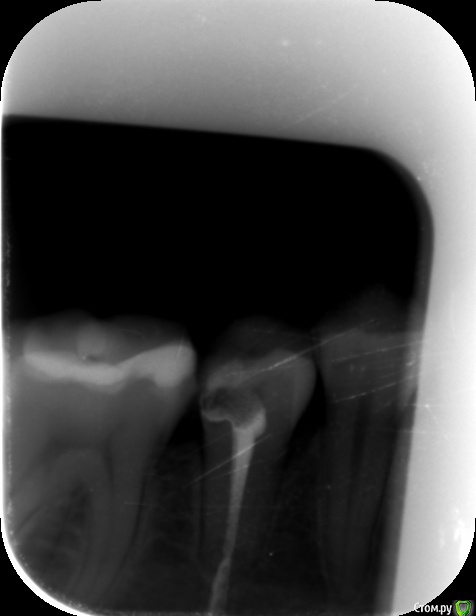

antemareundae Опубликовано 15 января, 2019 Поделиться Опубликовано 15 января, 2019 (изменено) Здравствуйте!Ситуация возникла очень неприятная и весьма непонятная для меня: 26 декабря 2018 года я пришла на прием в клинику в Санкт-Петербурге, чтобы вылечить 29 зуб (жалоб не было). Врач приняла решение о чистке каналов, поскольку, как она сказала, зуб достаточно "мягкий". Каналы после чистки закрыли временной пломбой ("Метапекс"), врач сказала прийти через 2-3 недели. Я взволновалась на следующий день, когда поняла, что ко мне не возвращается чувствительность. Часть губы, подбородка и десны не реагируют на прикосновения, температуру и прочее по сей день. К тому же, на десне рядом с зубом появился маленький гнойничок, которого, по моим наблюдениям, не было раньше (потом я поняла, что это свищ). Вчера, 14 января 2019 года, я пришла на повторный прием, врач сделала рентген (прикладываю к письму, кликнуть сюда), я описала все свои жалобы врачу, но её реакция была такой: "Всё пройдет, это нормально, приходи через месяц, часть пасты, которая вышла за пределы зуба, рассосётся".Дорогие специалисты, такое поведение врача адекватно? Мне кажется, у меня был периодонтит (хотя врач утверждала, что это пульпит), и она вывела пасту непреднамеренно. Я также прочла, это эта паста на масляной основе, она просто так с трудом рассасывается .Подскажите, как поступить правильно? Мне нужно обратиться к другому стоматологу-терапевту? Меня очень волнует эта ситуация и неврит, который появился вследствие вмешательства. Изменено 15 января, 2019 пользователем antemareundae Ссылка на комментарий

red_butler Опубликовано 15 января, 2019 Поделиться Опубликовано 15 января, 2019 Снимок не информативен Ссылка на комментарий

antemareundae Опубликовано 15 января, 2019 Автор Поделиться Опубликовано 15 января, 2019 Снимок не информативенНужно чётче корневую часть зуба? Ссылка на комментарий

red_butler Опубликовано 15 января, 2019 Поделиться Опубликовано 15 января, 2019 Нужно чётче корневую часть зуба?Наоборот Ссылка на комментарий

St. Опубликовано 15 января, 2019 Поделиться Опубликовано 15 января, 2019 Нужно чётче корневую часть зуба?Нужно чтоб корень поместился полностью Ссылка на комментарий

antemareundae Опубликовано 16 января, 2019 Автор Поделиться Опубликовано 16 января, 2019 у Вас врачебный стиль изложения.Вы-кто по профессии?Номер зуба уточните плз.Снимок до или после?Мне 21 год, я совсем не связана с медицинской сферой, обучаюсь гуманитарным наукам Зуб — 29, снимок сделан после. Ссылка на комментарий